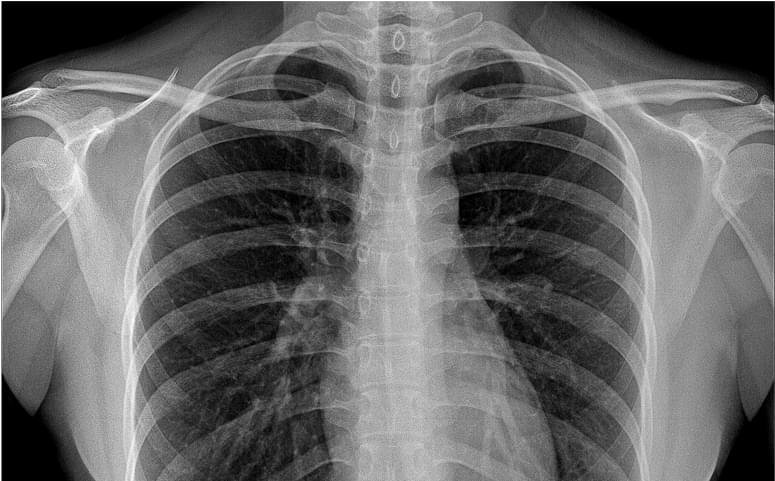

Chest X-rays are a routine first-line diagnostic test in both acute and outpatient care. Harrison.ai chest X-ray (CXR) helps identify incidental cancers, enabling crucial early detection and intervention.

- Identify up to 124 findings on chest X-ray.

- Including 10 findings related to cancer.